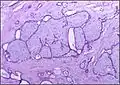

Macroscopic view of fibroadenoma of the breast

Macroscopic

Approximately 90% of fibroadenomas are less than 3 cm in diameter. However, these tumors have the potential to grow reaching a remarkable size, particularly in young individuals. The tumor is round or ovoid, elastic, and nodular, and has a smooth surface. The cut surface usually appears homogenous and firm, and is grey-white or tan in colour. The pericanalicular type (hard) has a whorly appearance with a complete capsule, while the intracanalicular type (soft) has an incomplete capsule.[9]

Fibroadenoma of the breast is a benign tumor composed of a biplastic proliferation of both stromal and epithelial components.[12][13] This biplasia can be arranged in two growth patterns: pericanalicular (stromal proliferation around epithelial structures) and intracanalicular (stromal proliferation compressing the epithelial structures into slit-like spaces).

These tumors characteristically display hypovascular stroma compared to malignant neoplasms.[2][14][9] Furthermore, the epithelial proliferation appears in a single terminal ductal unit and describes duct-like spaces surrounded by a fibroblastic stroma. The basement membrane is intact.[15]